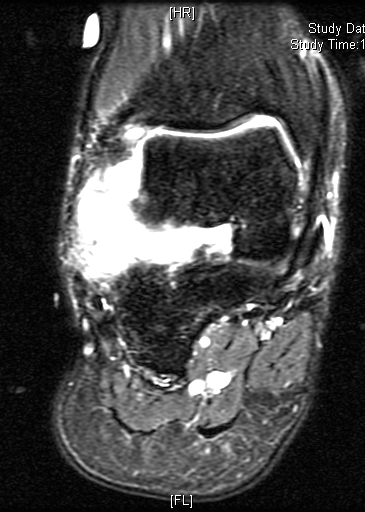

Shows multiloculated, heterogeneous mass.

“Triple Signal Intensity sign”; hypointense, isointense and hyperintense with fat on T2 – weighted MRI imaging. This sign is present in 30 to 50% of the cases. (Fig.3)

Under contrast enhancement Synovial Sarcoma appears heterogeneous and demonstrate areas of nodular enhancement.

In approximately 30% of cases a multiple vascular cannel may be identified

Synovial sarcomas may have a cystic appearance and are often mistaken for ganglion cysts especially those adjacent to tendons and in the foot and ankle.